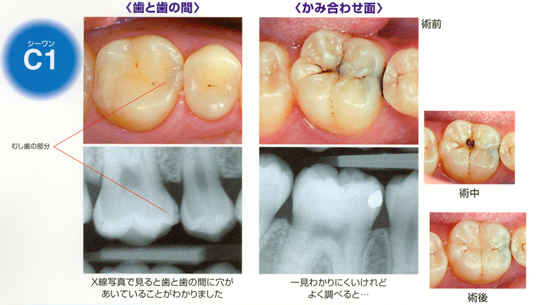

C1(シーワン)

歯の表面にあるエナメル質に小さな穴ができます。

痛みなどの自覚症状がほとんどないので、気付かないこともあります。